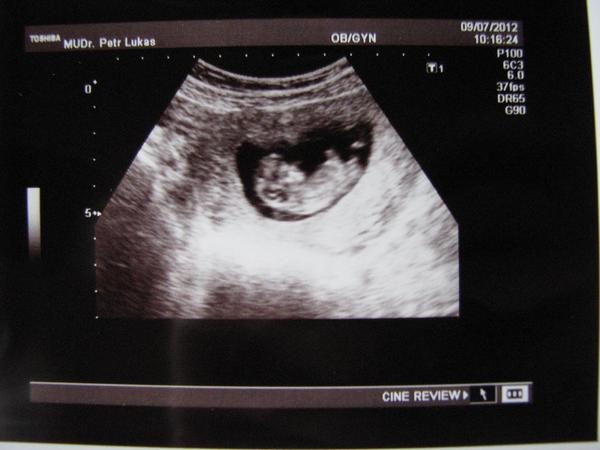

ahoooojte kočiny, takže se hlásím z dnešní kontroly 😉 mimčo roste jako z vody 😵

vyfasovala jsem konečně průkajdu, takže jsem ofiko těhule 😀 a jak jsem myslela,že dnes jsem 10+4, tak Dr. mi podle UTZ řekl že jsem prostě dnes 11+0... 😅 (asi jsme zas většíí). Vzali mi dnes krvičku a za 14dní jdu na UTZ na zjištění projasnění šíje. Takže se teď budu zas modlit aby bylo vše ok.

broučínka přikladám 😵 😵